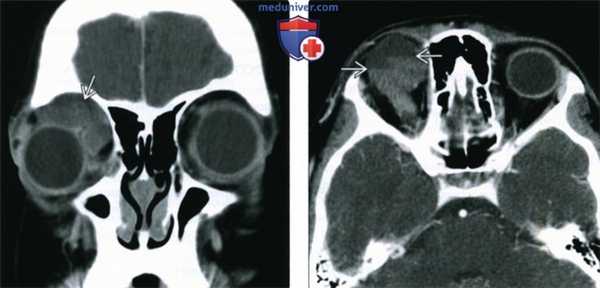

(Слева) У ребенка с периодически усиливающимся экзофтальмом при КТ с КУ в корональной проекции в верхнемедиальном квадранте переднего отдела глазницы определяется дольчатое образование от средней до низкой плотности, вызывающее смещение глазного яблока.

(Справа) При КТ с КУ в аксиальной проекции у этого же пациента в толще образования определяются множественные лакуны, содержащие жидкости различной плотности с отчетливыми уровнями. Более плотные длительно существующие продукты разложения крови оседают книзу.

(Слева) При КТ с КУ в аксиальной проекции в медиальной части левой глазницы определяется кистозное четко отграниченное неконтрастируемое образование, стенка образования неразличима. Хотя наблюдается картина простого однокамерного образования, оно лежит в нескольких смежных пространствах, имеет пресептальный компонент и компоненты внутри и вне мышечного конуса.

(Справа) При КТ без КУ в аксиальной проекции у четырехлетнего ребенка определяется неправильной формы многокамерная лимфатическая мальформация глазницы, распространяющаяся в несколько смежных пространств. Расслоение жидкостей с различными плотностями обусловлено оседанием продуктов распада крови, скопившихся при спонтанном кровоизлиянии.